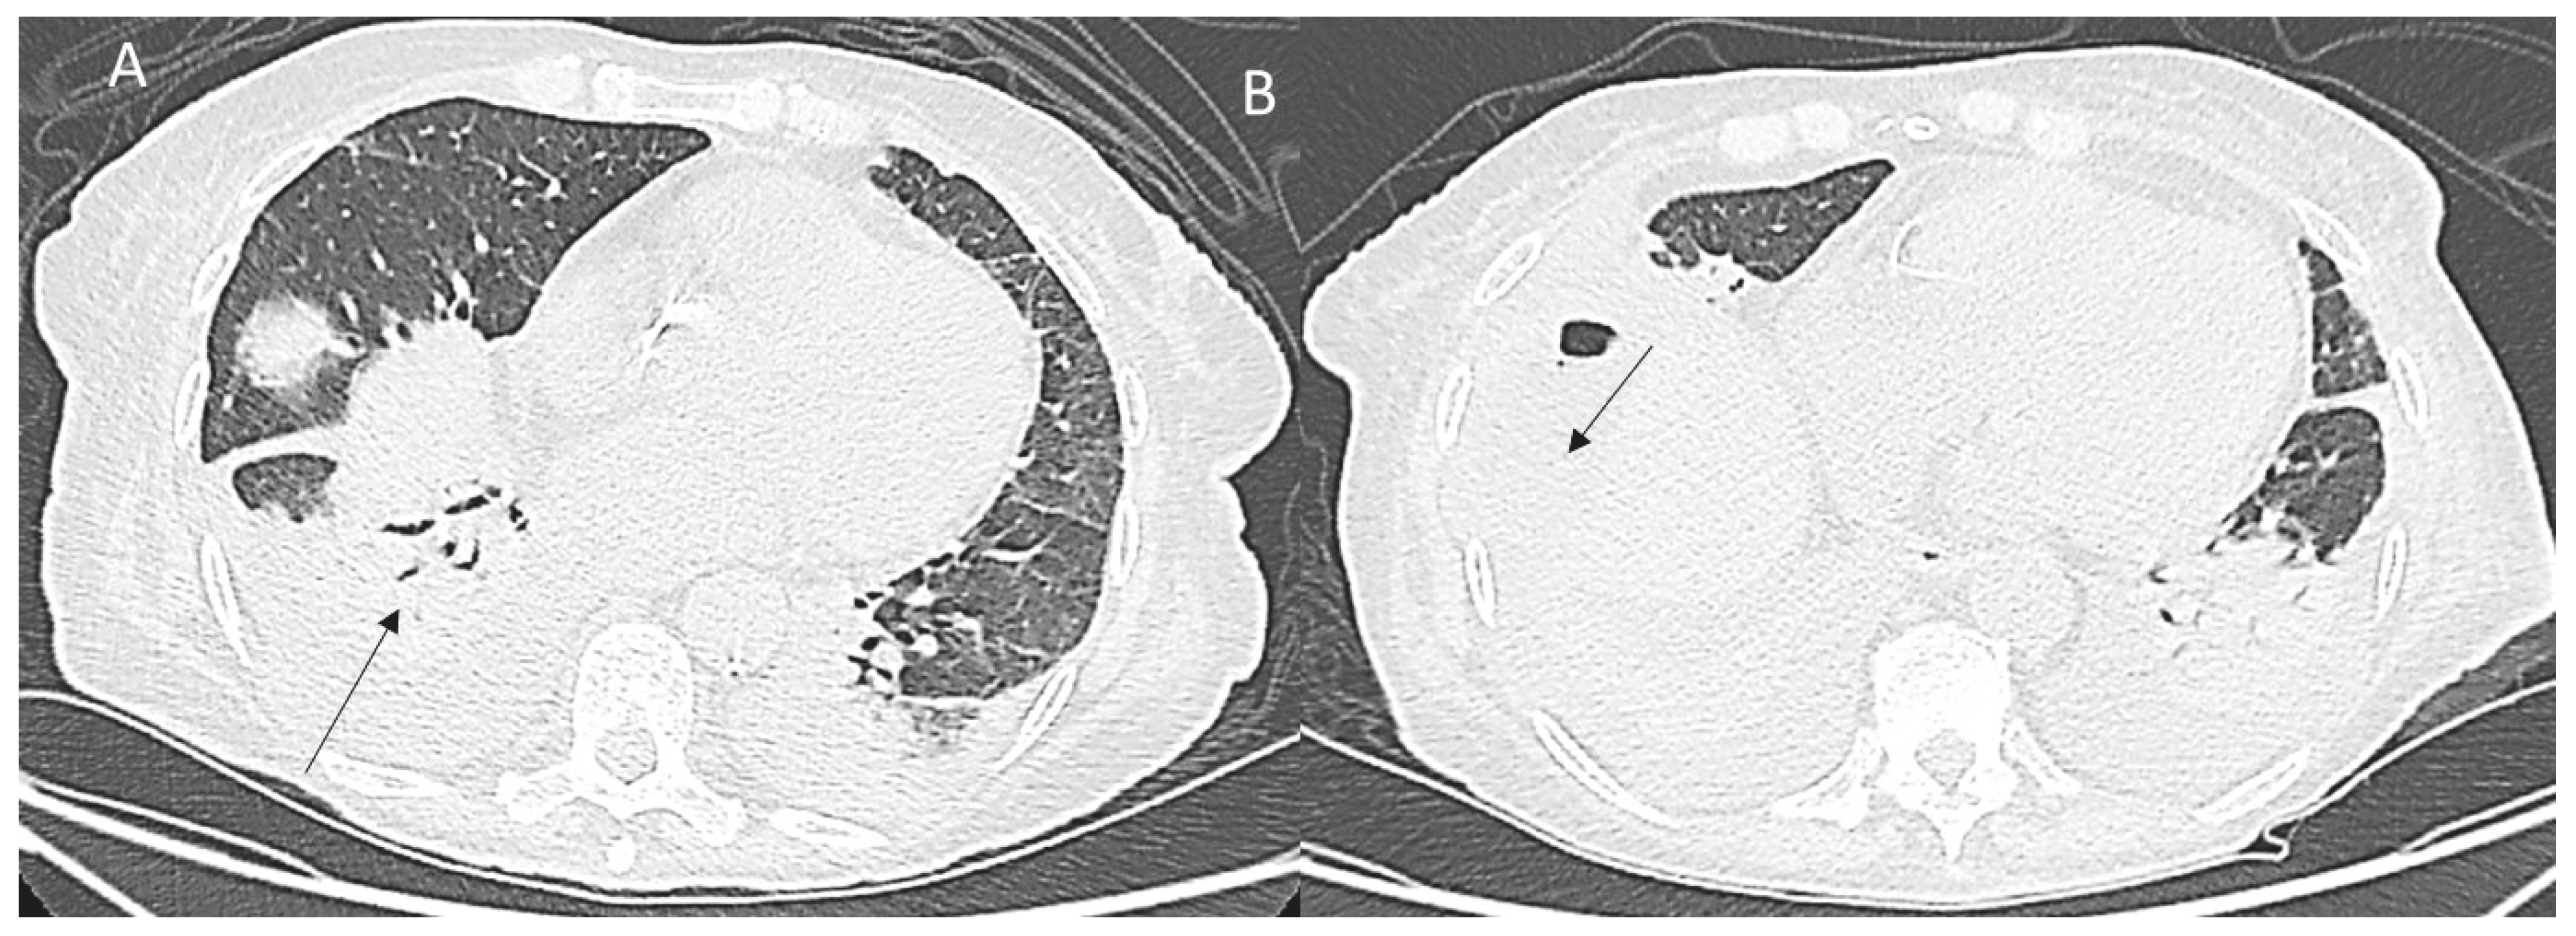

Figure 6. CT assessment (A,B) of treated HCC on IVa seg: pleural effusion and consolidation (arrow).

Thoracic complications may range from a right pleural effusion considered a paraphysiological sequela to severe pleural or diaphragmatic injuries [87] (Figure 6).

The risk of pleural damage increases during the treatment of masses located on the hepatic dome, choosing an intercostal approach.

If the patient complains dyspnea and breathing difficulties, it is appropriate to perform a chest X-ray, eventually followed by a CT scan.

A pneumo or haemothorax due to damage of diaphragmatic vessels may be easily detected and subsequently monitored or eventually treated.